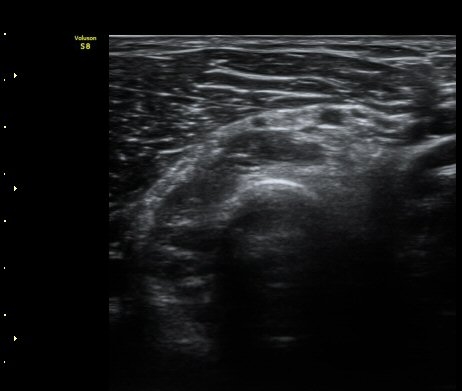

ÃÊÀ½ÆÄ °Ë»ç